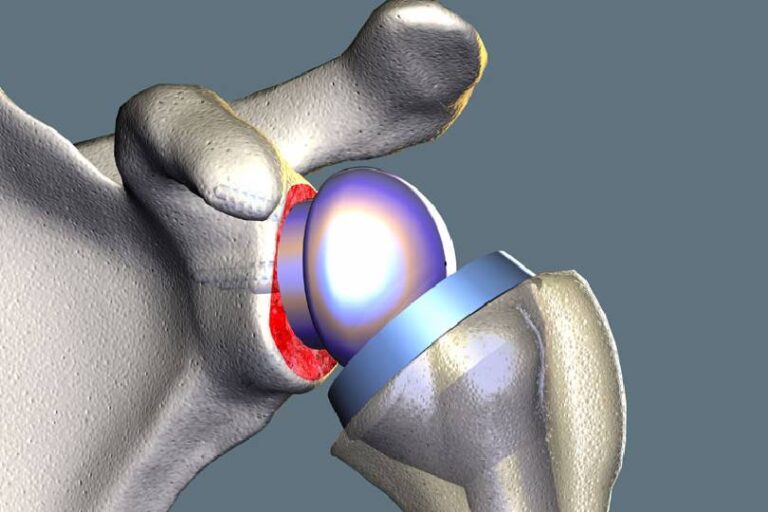

Shoulder Replacement Surgery

Shoulder replacement surgery, also known as shoulder arthroplasty, is a surgical procedure aimed at relieving pain and restoring function.

Shoulder replacement is recommended for patients with severe shoulder arthritis, fractures, or rotator cuff injuries causing chronic pain and stiffness. The damaged joint surfaces are replaced with artificial components to restore shoulder strength and motion.